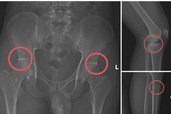

Tự đục vỡ xương để “qua mặt” bảo hiểm